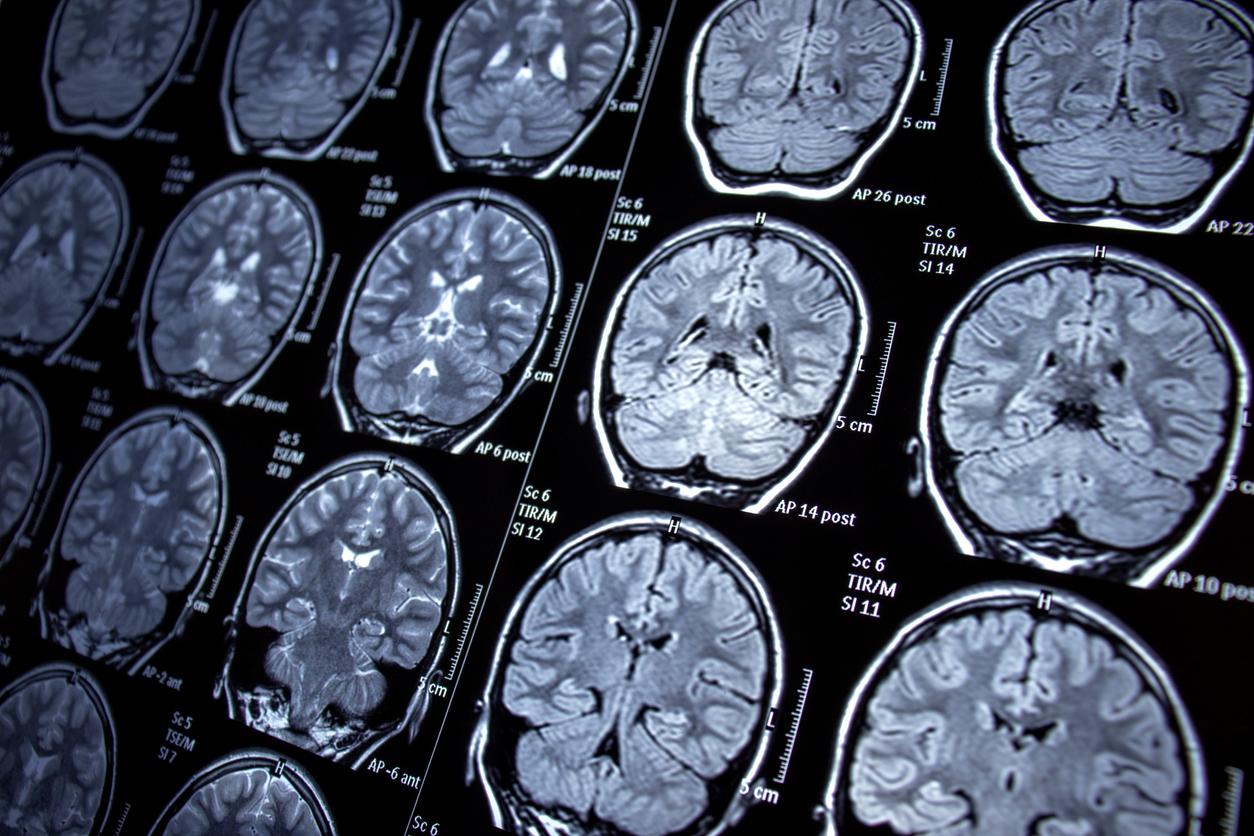

Et, justement, une récente étude publiée dans la revue Frontiers in Human Neuroscience vient de trouver une piste intéressante. Les chercheurs qui en sont à l'origine ont réussi à mettre au point un dispositif capable de restaurer, en partie, la mémoire des patients atteints de lésions dans le cerveau. Il s’agit d’électrodes cérébrales qui imitent l’hippocampe - la zone touchée en cas de troubles de la mémoire - et stimulent l’encodage des souvenirs.

Pour tester leur appareil, les chercheurs ont mené un essai clinique sur 24 patients atteints d’épilepsie réfractaire, c’est-à-dire résistante aux traitements. Cette maladie qui touche le cerveau regroupe différents symptômes mais la manifestation la plus typique de l’épilepsie est la crise épileptique, dont on distingue deux types : la crise généralisée et la crise focale, selon l'Institut national de la santé et de la recherche médicale (Inserm). Les participants souffraient également de lésions cérébrales.

Tous les participants ont été équipés d’électrodes cérébrales et leur capacité mémorielle a été évaluée lors des tests. Lors de ces derniers, ils devaient observer une image - quand c’était la première fois, les électrodes s’activaient - et la reconnaître 15 à 90 minutes plus tard.

Durant cette deuxième étape, quand le cerveau des participants devait reconnaître l’image, les électrodes cérébrales reproduisaient les signaux électriques de l’hippocampe. "Notre stimulation structurée de l'hippocampe pendant l'encodage [de nouveaux souvenirs] améliore le rappel et la reconnaissance jusqu'à 90 minutes plus tard”, explique le professeur Robert Hampson dans un communiqué.